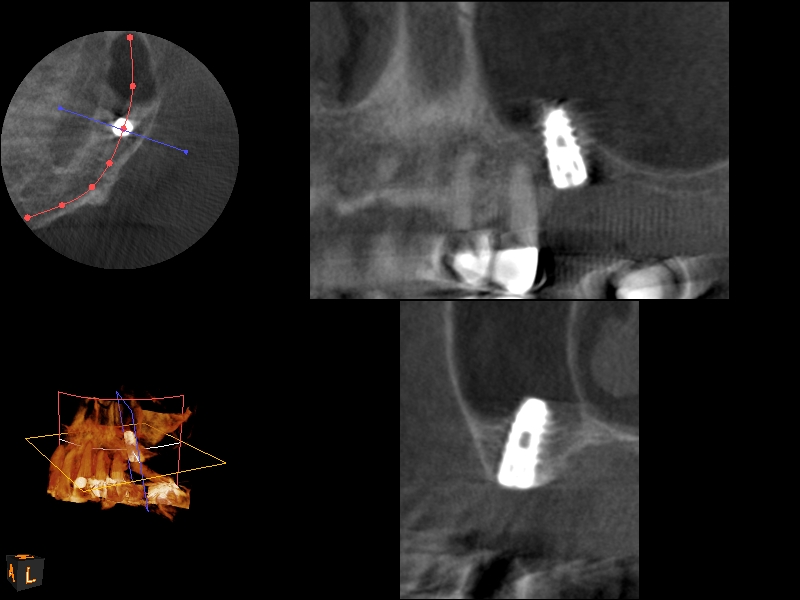

CBCT scan (Kodak 9000D) showing 3.5-month postoperative of implant No. 3 in place. Note homogeneous appearance of the bone.

Fig. 12

The implant is then delivered and should be well stabilized in the bone. If there is any mobility of the implant, it can either be placed a little deeper (if there is enough native bone) or the implant can be removed and the procedure aborted, in which case it would be a two-stage procedure. This should rarely occur with the tapered designed implant, even with only 2 mm of native bone. Using a bone-level platform-shifting implant (or a tissue-level designed implant) is critical, as the hard and soft tissue will establish a biologic width. If an external hex type of implant is used and the shoulder is placed at the bone level, an expected bone loss of 1.5 mm to 2 mm will occur.24 Figure 10 shows proper bone-level implant depth placement with a platform-shifting design. In this case, a 3-mm healing abutment was placed at the time of surgery to avoid a secondary uncovering surgery, but an implant-level healing abutment could have been placed instead. As can be seen, there was only about 2 mm to 3 mm of native bone height. The membrane was raised about 8 mm to 9 mm. Comparing the radiograph on the day of surgery (Figure 10) to the 6-month postoperative radiograph (Figure 11) shows no loss of native bone, as well as the positive change in appearance of the grafted bone. The 3.5-month CBCT scan (Figure 12) shows good healing of the bone with no coronal bone loss. With minimal native bone present, as in this case, the use of a non-platform-shifting or non-tissue-level implant design could be problematic. After 1.5 mm to 2 mm of crestal bone loss, an external hex designed implant could develop instability with possible implant failure. If a non-tapered implant is used and bone loss occurs during healing, migration of the implant into the sinus could potentially occur. The surgeon can use either a healing abutment or implant-level closure screw over the implant shoulder. With patients who tend to use their tongues to explore or play with the area, or if the area is under a removable partial denture, a closure screw is recommended.